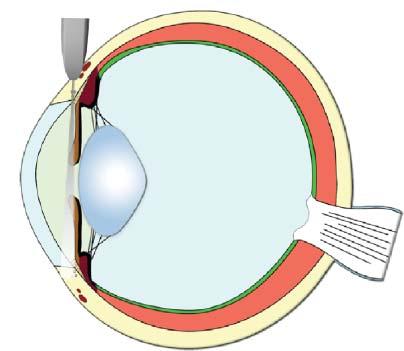

UltrasoundProbes andResolution

Ultrasoundprobes varyinconfigurationsforspecific needs(Figure1.4).Curvedlinearprobes,alsocalled convexormicroconvex,haveoneorseveralrowsof piezoelectriccrystalsalignedalongaconvexsurface, withvaryingbeamsandtracks.Theseprobesproduce

atriangularimagebecauseofthediverginglinesof ultrasoundwavestheygenerate.Themainassetsof thistypeofprobeareitssmallerfootprintanditslarge scanningfield,makingittheidealprobeforassessing theabdomen,particularlythecranialportionalong

theribcage.Thepiezoelectriccrystalsofthelinear probesaredistributedalongaflatsurface,producing arectangularscanfield.Thephaseintervalofthe impulsionscanalsoproduceatrapezoid-shaped image,allowingittocoveralargersurface.Thisis

Figure1.4. Practicalultrasoundtransducers. Mostultrasoundunitsareequippedwithconvex (A,B) andlinear (C) electronictransducerswithvariablefrequencies.Amacroconvexprobe (A) offeringlowerfrequencies(3–8MHz)isbestsuitedfor theabdomenoflargedogs,whereasamicroconvexprobe (B) ofhigherfrequencyandsmallerfootprintispreferredforthe abdomenofsmallpatientsandwhenonlyasmallacousticwindowisavailable(e.g.,theintercostalapproachofalunglesion). Ahigh-frequency(10–18MHz)linearprobe (C) ismostusefulforassessingsuperficialstructuresonarelativelywideandflat surface(e.g.,assessingbowelsinacat,bicepstendoninadog).Aphasedarraytransducer (D) offersasmallflatfootprintand isidealforechocardiography.

especiallyusefulwhenevaluatingsuperficialorgans whosediametermaybegreaterthanthewidthofthe scannedarea,suchasthekidneysandspleen.The lengthoftheprobe’sfootprintindicatesthewidthof theareaitscans.